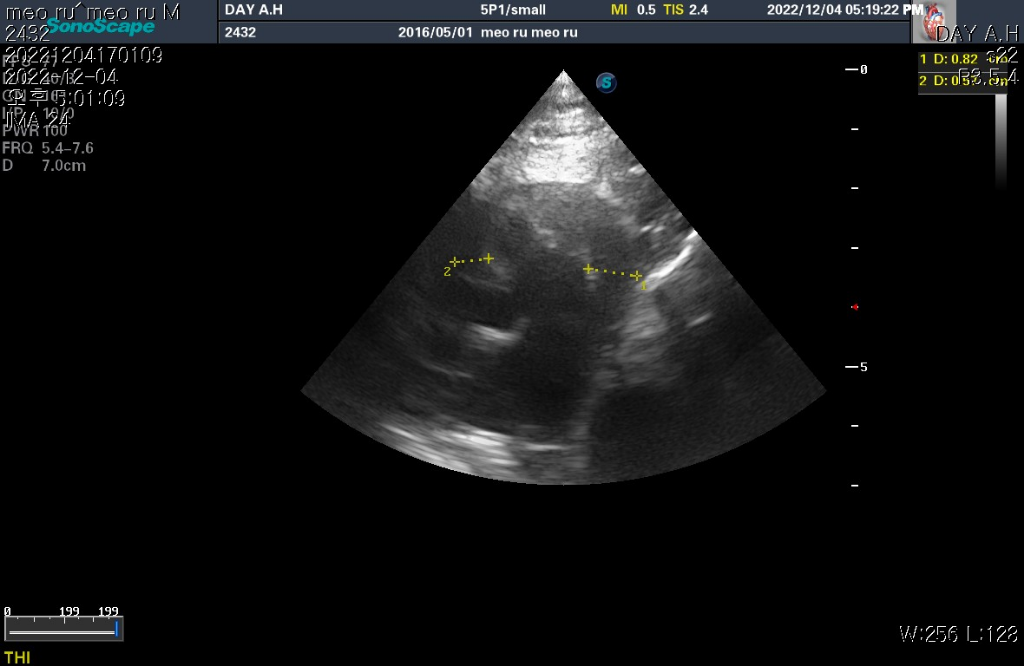

하지만 심장 질환의 잠정적 확진 golden standard는 심장 초음파 검사로 심장 초음파 검사상 심장의 벽 구조가 6mm이상이라면 HCM의 가능성이 매우 높다고 판단합니다.

현재 첨부한 사진상에서 6mm이상의 직경을 보이는 사진들이 존재하기 때문에 해당 검사를 진행한 수의사의 기준상 HCM의 가능성이 높다고 판단하는것은 합리적입니다.